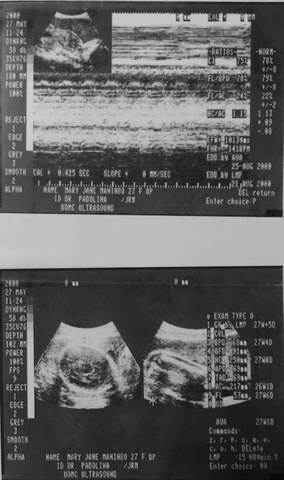

This is the first picture taken of me. The ultrasound scan my mom took while carrying me in her womb. Not many people realize this but we were exposed to various forms of media since we were inside the womb.

An ultrasound scan, sometimes called a sonogram, is a procedure that uses high-frequency sound waves to create an image of part of the inside of the body. (https://www.nhs.uk/conditions/ultrasound-scan/)